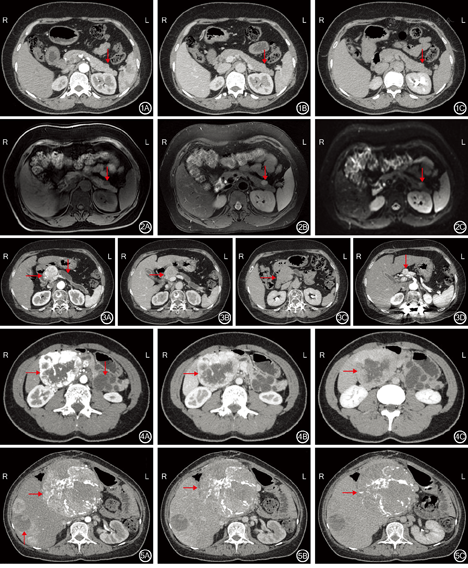

20例功能性pNENs患者,肿瘤直径为0.6~3.0 cm,平均肿瘤直径为1.5 cm。肿瘤部位:胰头部4例,胰体部10例,胰尾部6例。20例功能性pNENs患者中,19例肿瘤边界清楚,1例肿瘤边界欠清晰。20例功能性pNENs患者中,18例肿瘤密度均匀,2例肿瘤密度不均伴囊变,肿瘤均不伴有钙化。20例行动态增强扫描:19例肿瘤动脉期强化明显,门静脉期及延迟期强化程度稍高或等于正常胰腺组织,1例肿瘤动脉期呈弱强化、门静脉期及延迟期强化程度等于或稍低于正常胰腺组织。见图1。3例患者行MRI扫描检查患者:肿瘤均表现为脂肪抑制T1加权成像呈低信号,T2加权成像呈高信号,DWI(b=1 000 s/m2)高信号,肿瘤显示清晰。见图2。20例患者中,1例伴有肿瘤远端胰腺组织萎缩、胰管扩张、多发潴留囊肿及肝总动脉旁淋巴结肿大(图3)。

13例无功能性pNENs患者,肿瘤直径为1.5~16.0 cm,平均肿瘤直径为5.0 cm。肿瘤部位:胰头部6例,胰腺钩突部1例,胰体部3例,胰尾部3例。13例无功能性pNENs患者中,11例肿瘤边界清晰,2例边界不清晰。13例无功能性pNENs患者中,3例肿瘤密度较均匀,10例密度不均,伴有囊变(图4)。13例无功能性pNENs患者中,2例肿瘤伴有钙化(图5)。13例行动态CT增强扫描患者:其中12例肿瘤动脉期强化明显,门静脉期及延迟期持续性强化,囊变区强化不明显,部分肿瘤可见明显增粗的供血动脉及引流静脉(图6, 图7);1例肿瘤强化较弱,三期强化程度均稍低于正常胰腺组织,边界不清晰(图8)。6例患者行MRI扫描检查,4例患者肿瘤脂肪抑制T1加权成像呈低信号,T2加权成像呈稍高或混杂信号,DWI(b=1 000 s/m2)呈高信号;2例患者肿瘤脂肪抑制T1加权成像呈低信号,T2加权成像呈低信号,DWI(b=800 s/m2)呈稍高信号(图9)。13例无功能性pNENs患者中,4例出现胆管及胰管扩张(图10,图11)。7例无功能性pNENs患者出现局部组织侵犯或远处转移(肝脏转移4例、胰腺周围淋巴结转移1例、肝脏和胰腺周围淋巴结同时转移1例,肝脏转移及脾动静脉侵犯1例),其中G1级1例,G2级4例,G3级2例。5例肿瘤直径>5.0 cm患者中,4例出现肝脏或淋巴结转移。